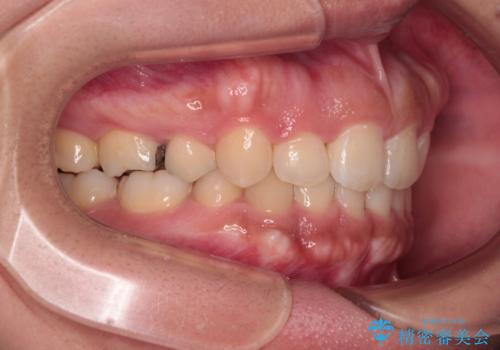

急速拡大とワイヤー抜歯矯正で唇を閉じやすく

- 口元の突出感を気にして来院された患者様です。

デコボコと口元の突出感が認められたため、上下左右の第1小臼歯4本を抜歯してのワイヤー矯正を行うこととしました。

上顎歯列の横幅が狭く、下顎大臼歯の歯軸が舌側に倒れていたため、急速拡大装置により上顎骨を側方に拡大し、咬み合わせを改善することとしました。

上顎歯列幅を拡大したことで、デコボコを容易に解消することができるようになったため、抜歯により得られたスペースを口元の突出感改善に利用することができました。